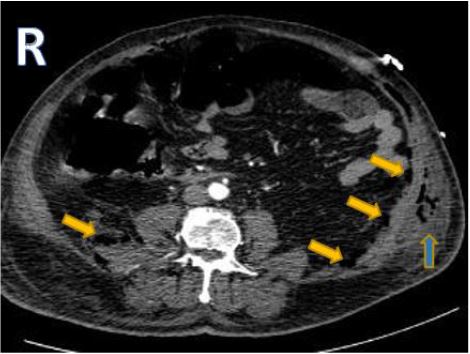

Contrast enhanced Computed tomography (CECT) performed in dual phases of contrast enhancement with nonionic iodine based intravenous contrast and arterial bolus tracking technique. Using In the arterial phase, 120 kV and 304 mA was used, whereas, in the venous phase 140 kV and 200 mA was used. Two slices with thickness of 2 mm and 3 mm were used for the arterial and venous phase, respectively. CECT revealed abdominal wall emphysema (Figure 1) and right iliac fossa inflammatory changes around the caecum manifested as para-colic fat stranding and thickened hyper enhanced appendix wall with increased cross-sectional diameter reaching 14.5 mm (Figure 2). Associated extensive pneumoretroperitoneum and abdominal wall inflammatory edema (figure 3) was detected; however, no evidence of penumoperitoneum.

Figure 3: Axial contrast enhanced computed tomography scans of the abdomen showing abdominal wall emphysema and inflammatory edema notably on the left side (blue arrow) and retropneumoperitoneum (yellow arrows)